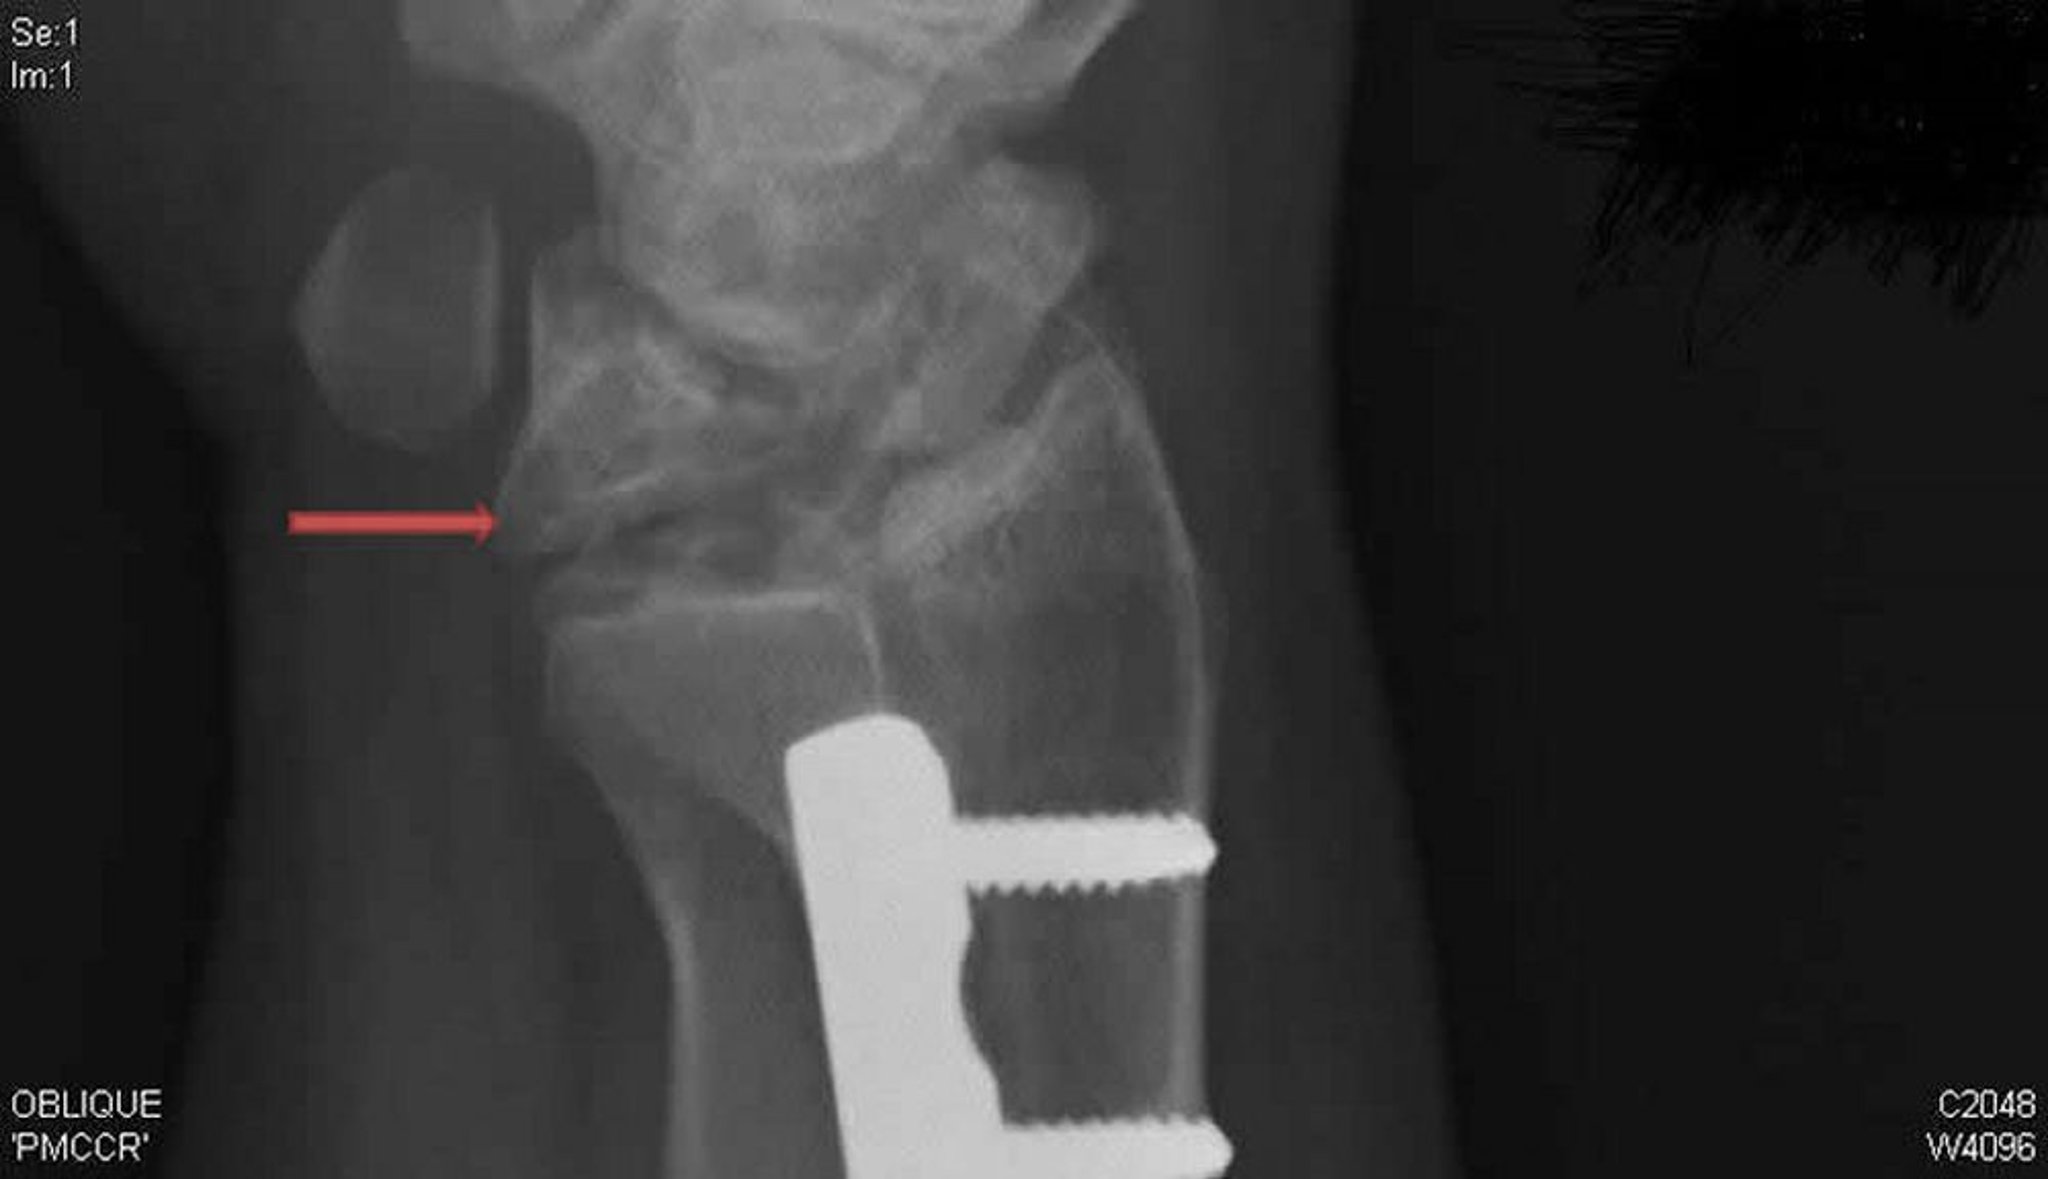

Để chẩn đoán bệnh Kienböck, chụp MRI và chụp CT là nhạy nhất; X-quang cho thấy những bất thường muộn hơn, thường bắt đầu bằng xơ cứng xương nguyệt, sau đó là các nang thay đổi, phân mảnh và xẹp.

Phim chụp X-quang do bác sĩ David R. Steinberg cung cấp